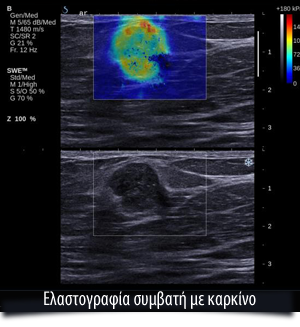

Η πλέον σύγχρονη τεχνική είναι η Shear Waves, με την οποία η εικόνα αποκτά μια νέα δυναμική και απαλλάσσει τον ασθενή αλλά και τον ακτινολόγο από την πίεση της κεφαλής των υπερήχων. Με τη νέα μέθοδο η κεφαλή, αφού απλά σταθεροποιηθεί πάνω από τη βλάβη, στέλνει ήχους, οι οποίοι επιστρέφουν δημιουργώντας ένα κύμα παραμόρφωσης στη βλάβη, το οποίο και αναλύεται από την ίδια την κεφαλή. Η μέθοδος αυτή έχει δύο πολύ σημαντικά πλεονεκτήματα. Εκτός του ότι είναι και ποσοτική και όχι ποιοτική, είναι και αντικειμενική, διότι δεν εξαρτάται από τον χειριστή του μηχανήματος και τον βαθμό πίεσης που θα εξασκήσει, αλλά από την αυτόματη μέτρηση της κεφαλής.

Η μέτρηση γίνεται σε Kilopascal και το όριο είναι 72 kilopascal. Πάνω από αυτό το όριο, η βλάβη χαρακτηρίζεται ως κακοήθης.